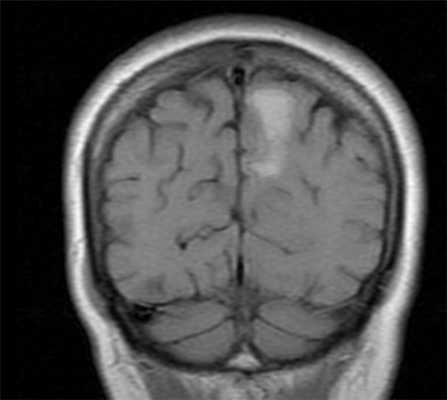

![смешанный]()

МРТ головного мозга. Т1-взвешенная корональная МРТ. Смешанный ишемический инсульт. Ранняя подострая стадия.